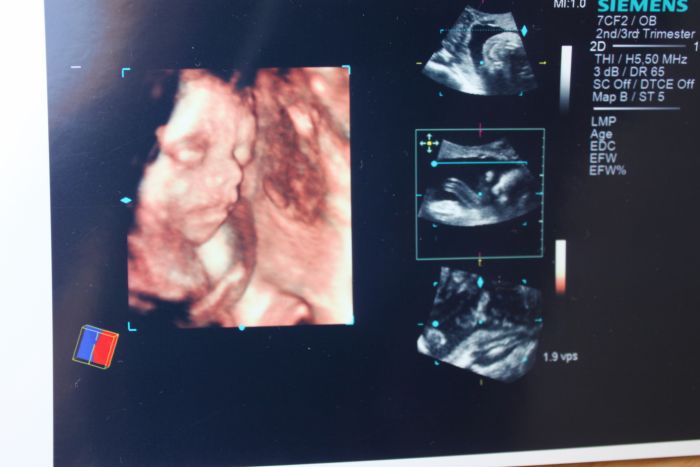

Ahoj holky. Tak já dnes byla u Dr. Vše je ok. Ovšem pak jsem jela na 4D ultrazvuk. To byla paráda..jsem nadšená, malej byl úžasnej. Nejdřív se moc nechtěl ukázat, ručičkou se schovával, ale pak se předvedl v plné kráse. Je to kulíšek roztomilej. Mám fotky i DVD, ale fotky jen vytištěný, tak vám je nemůžu ukázat...

ale můžeš! Nafoť je foťákem, já to tak taky dělám, vypadaj jako pravý

[143646] Tak já to zkusím :-)